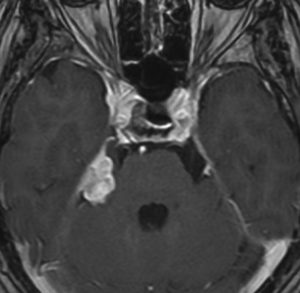

放射線誘発膠芽腫(グリオブラストーマ)

放射線治療10年後です。側脳室の中の腫瘍は小さくなって再発はありませんが,脳幹部と小脳に膠芽腫が発生しました(右側のMRI)。この腫瘍も放射線誘発腫瘍と考えられます。脳幹部の膠芽腫は助かることがない悪性腫瘍です。